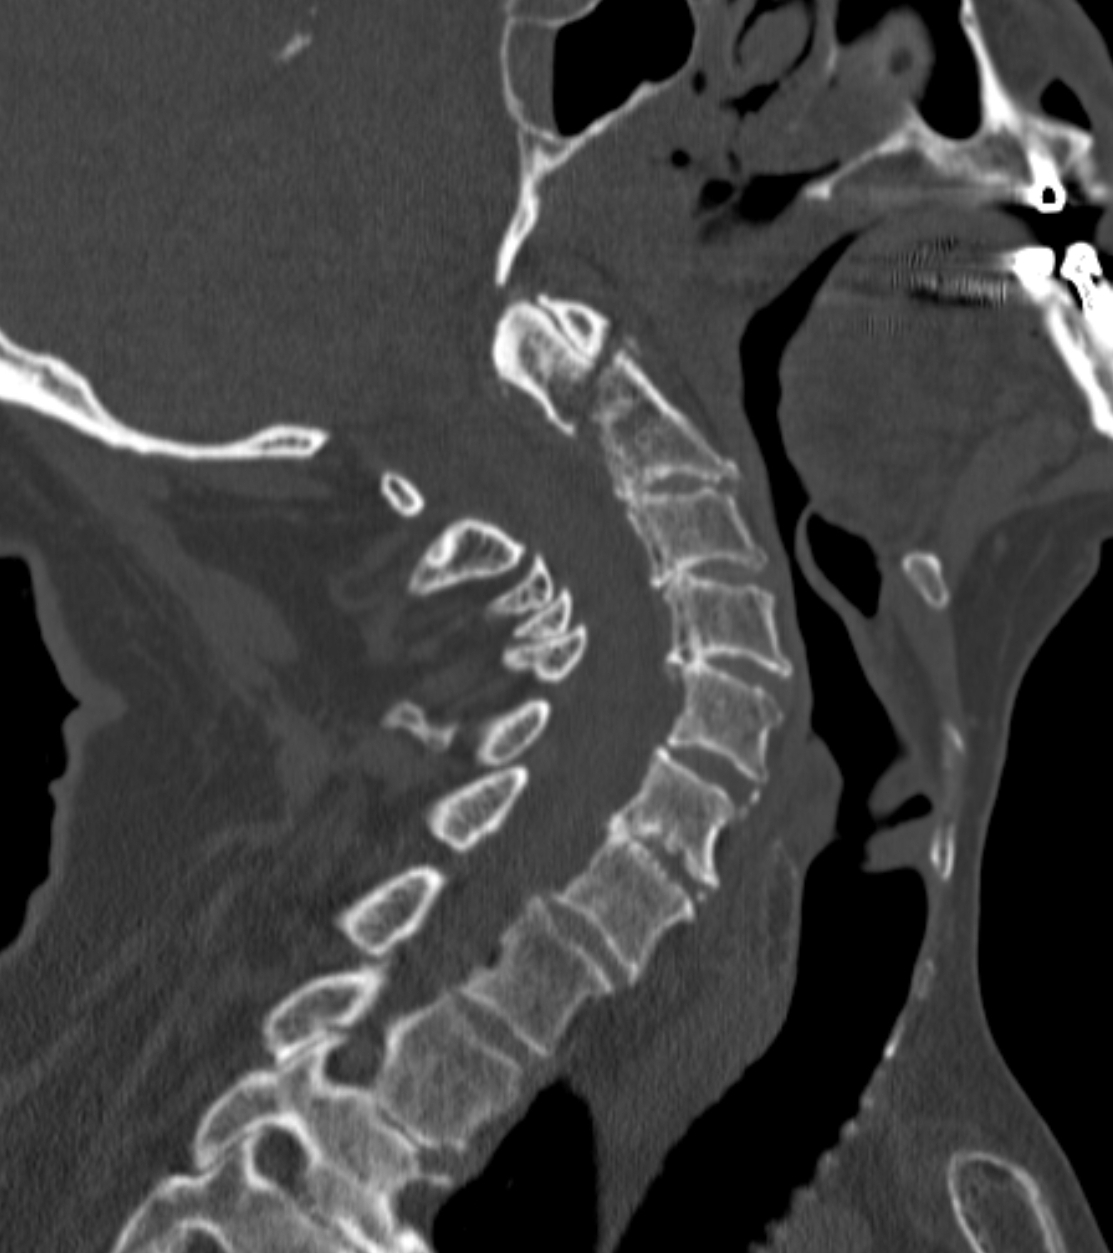

Male. Age 28. Fell whilst drunk.

A confusing clinical picture. Unable to obtain an accurate or reliable clinical history and very difficult to assess the clinical signs.

Are these radiographs normal or abnormal?

RADIOGRAPHS